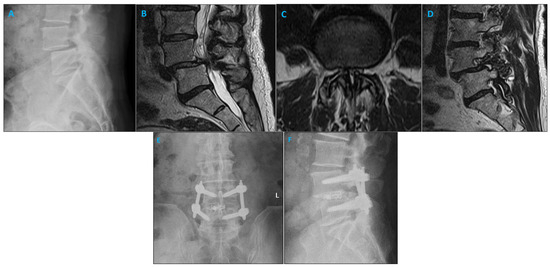

2.2. Surgical Approach

4. Discussion